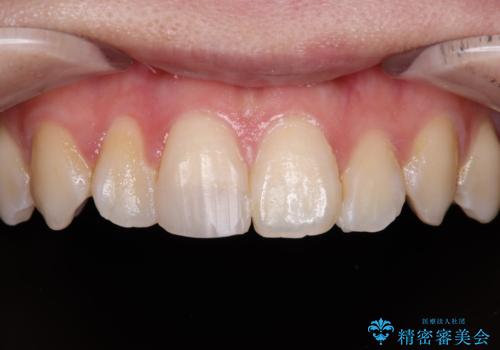

違和感のある前歯をセラミックにしたい

- 前歯が欠けてしまい、保険診療の樹脂の材料で修復していた前歯をきれいにしたいと来院された患者様です。

歯の約半分が欠けてしまっているため、樹脂の材料での修復には限界があります。

樹脂の材料では再現できない自然な前歯に仕上がりました。